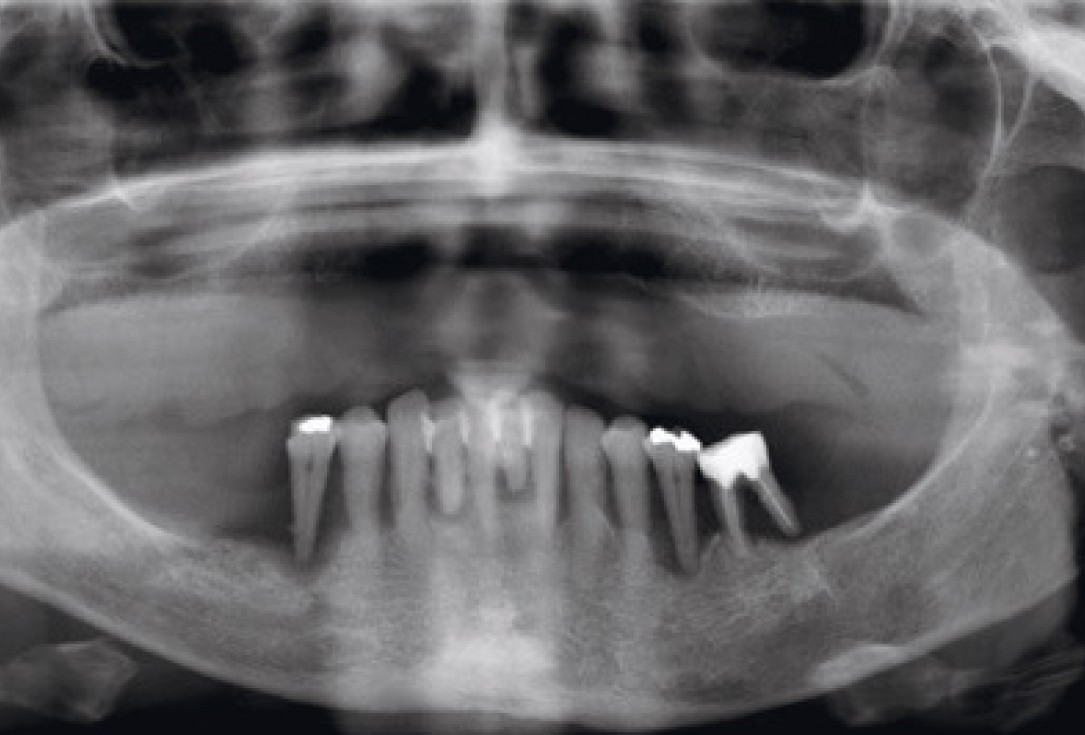

01/11 - Pre-operative OPG of the patient